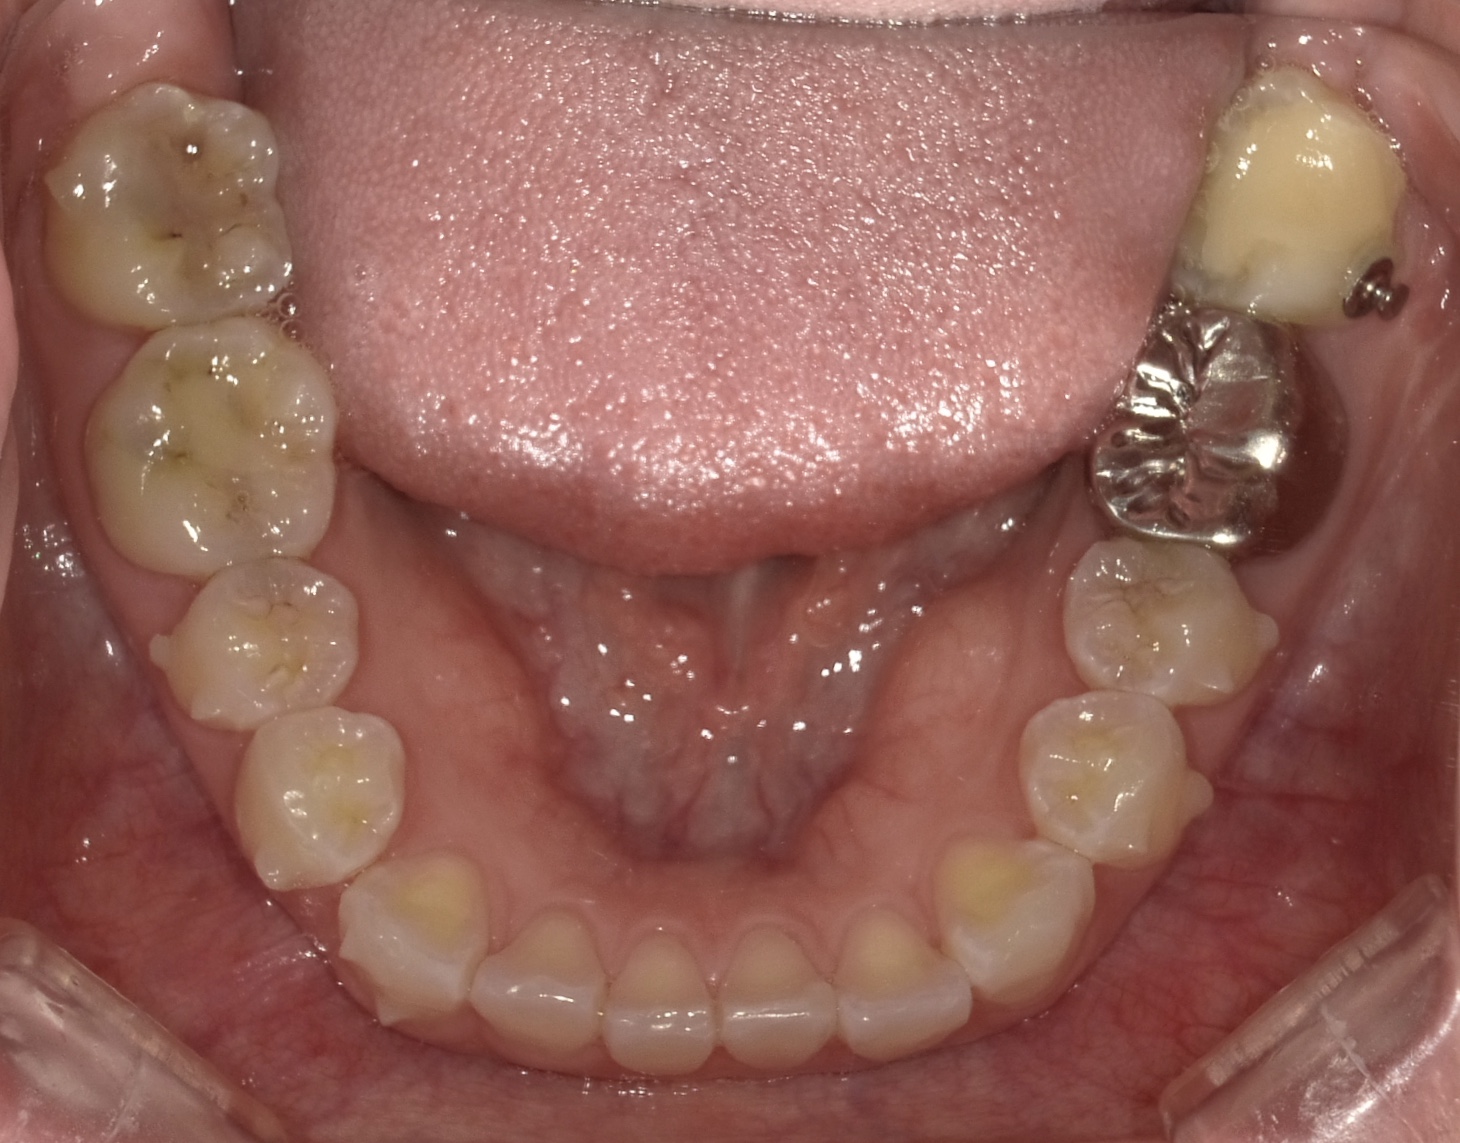

矯正スタート時(下顎)撮影:2018.07↓ 矯正7ヶ月経過(下顎)撮影:2019.04↓

下顎はきれいに並んできたと思います😁